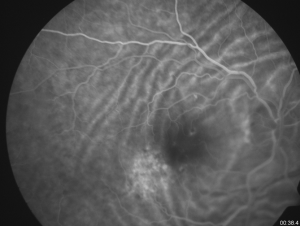

The diagnosis is made mainly by fluorescein angiography, wherein the folds appear as a series of alternating hyperfluorescent and hypofluorescent streaks starting early in the arteriovenous phase, persisting through the late venous phase, and not leaking in the late films. The hyperfluorescent areas correspond to the peaks of the choroidal folds, and the hypofluorescent areas to the valleys.[3]

Fluorescein angiography cannot differentiate chorioretinal from choroidal folds, but the optical coherence tomography (OCT) patterns of the two are strikingly different although these are not completely singular entities. In cases of chorioretinal folds, OCT shows that the retina, RPE and choroid are all folded in a similar manner and maintain their normal relationships and apparently normal thickness, although a certain flattening of the inner retina can be seen along the crests, whereas choroidal folds correspond to undulations of the hyperreflective line corresponding to the RPE as well as the underlying choroid with a flat or nearly flat retinal surface with a variable retinal thickness variable, increasing in correspondence to the valleys and reducing in the crests. The retina, which has a softer structure, adapts itself to the wrinkling to preserve a flat inner surface.[19] The severity of choroidal folds have been staged on the basis of FA imaging. [28]

The characteristic fluorescein pattern of hyperfluorescent bands alternating with hypofluorescent bands noted in choroidal folds allows a clear distinction from retinal folds where no such pattern is seen on the FA.[15]